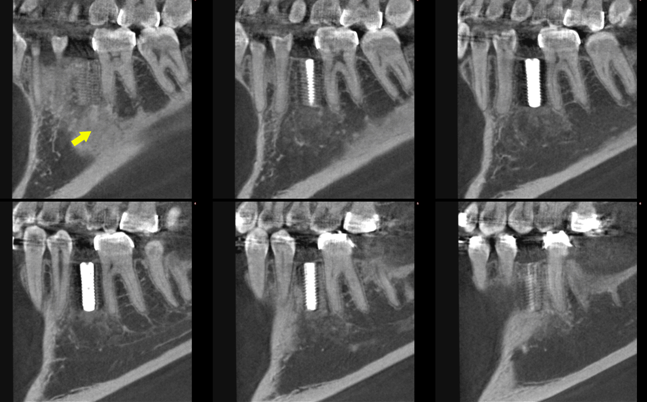

Figure 5: Mapping of mandible arch in sagittal view using cone beam computed tomography represents the dental implant (location at area of extracted tooth #35) was fully integrated and showed good healing of bone grafts (yellow arrow). No abnormality in radiographs was noted.